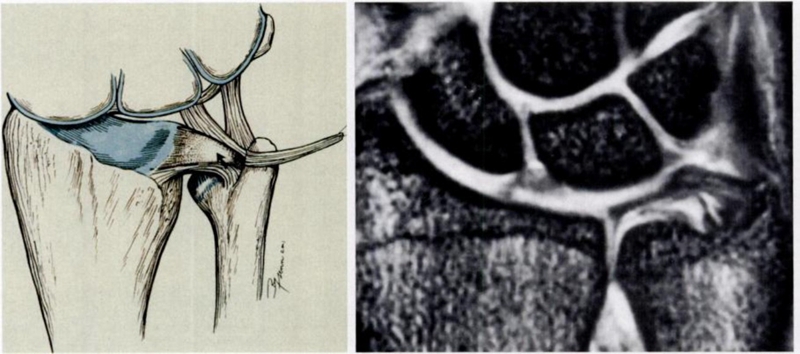

ⅠC,尺三角韧带撕裂